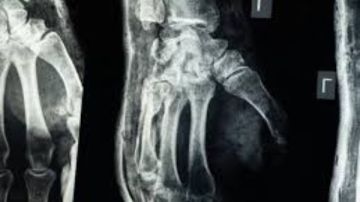

ابتكار صيني ثوري .. لاصق طبي يصلح العظام المكسورة في 3 دقائق فقط